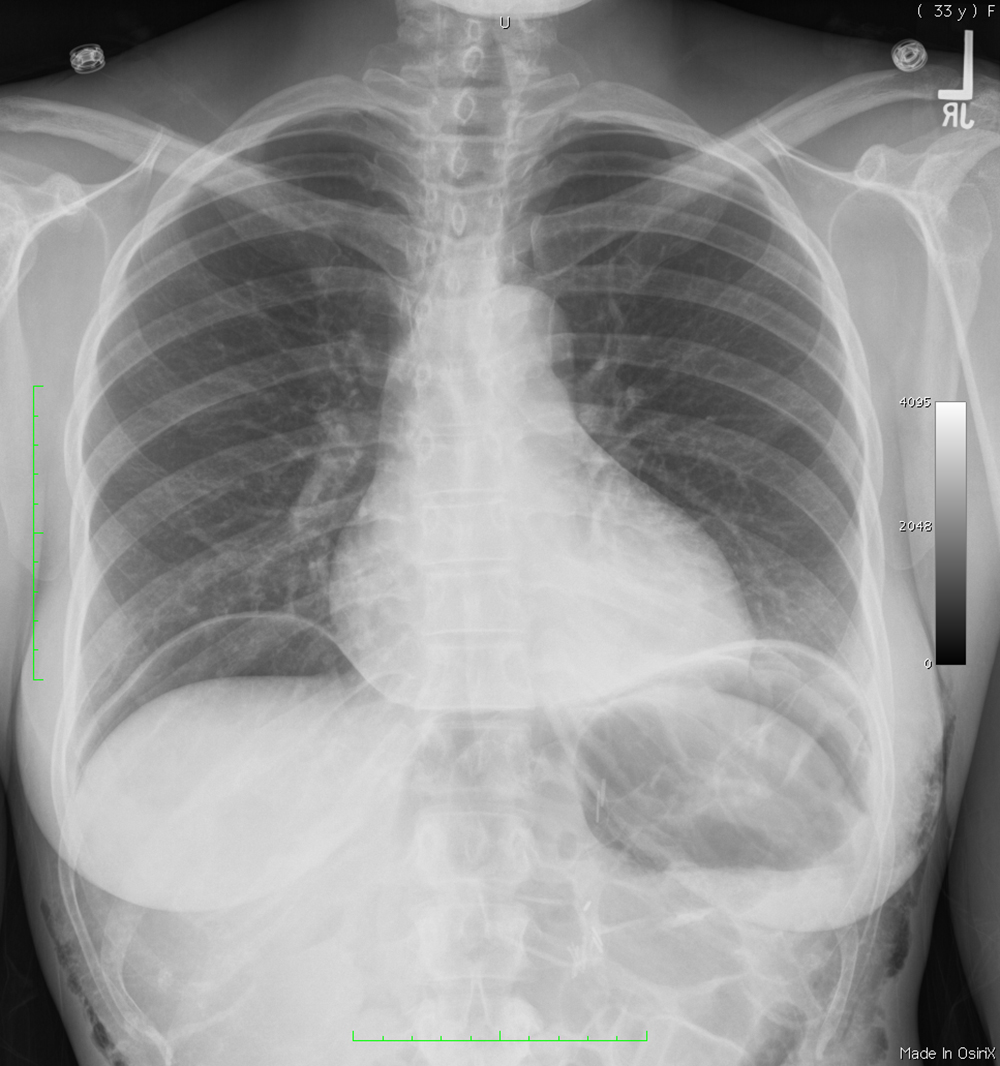

alternative diagnosis for other abnormal air